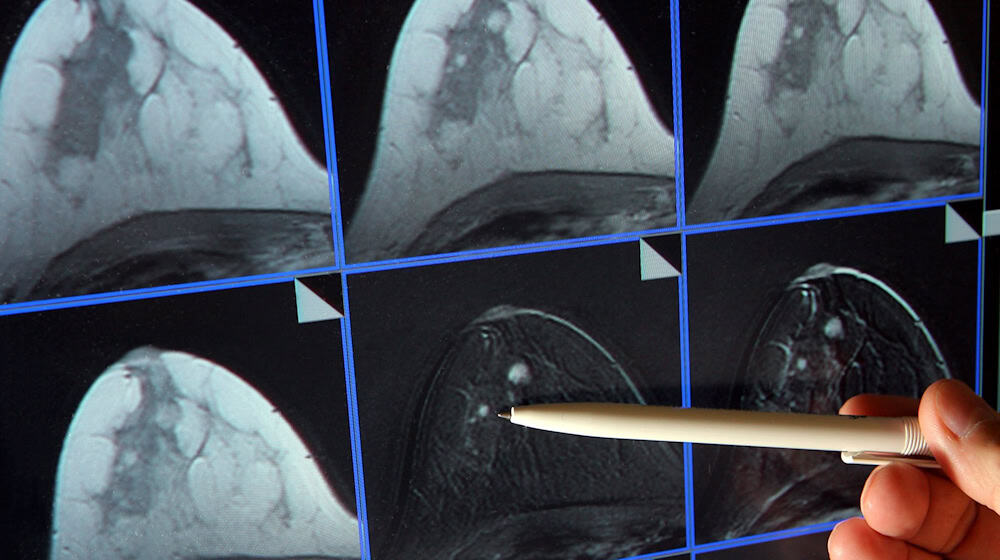

Mit einem Mammographie-Screening kann Brustkrebs zeitig entdeckt werden. (Symbolbild) / Foto: Jan-Peter Kasper/dpa-Zentralbild/dpa